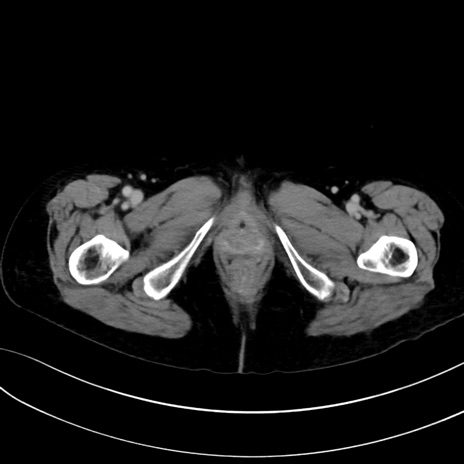

症例13 CT(横断像)1日半後